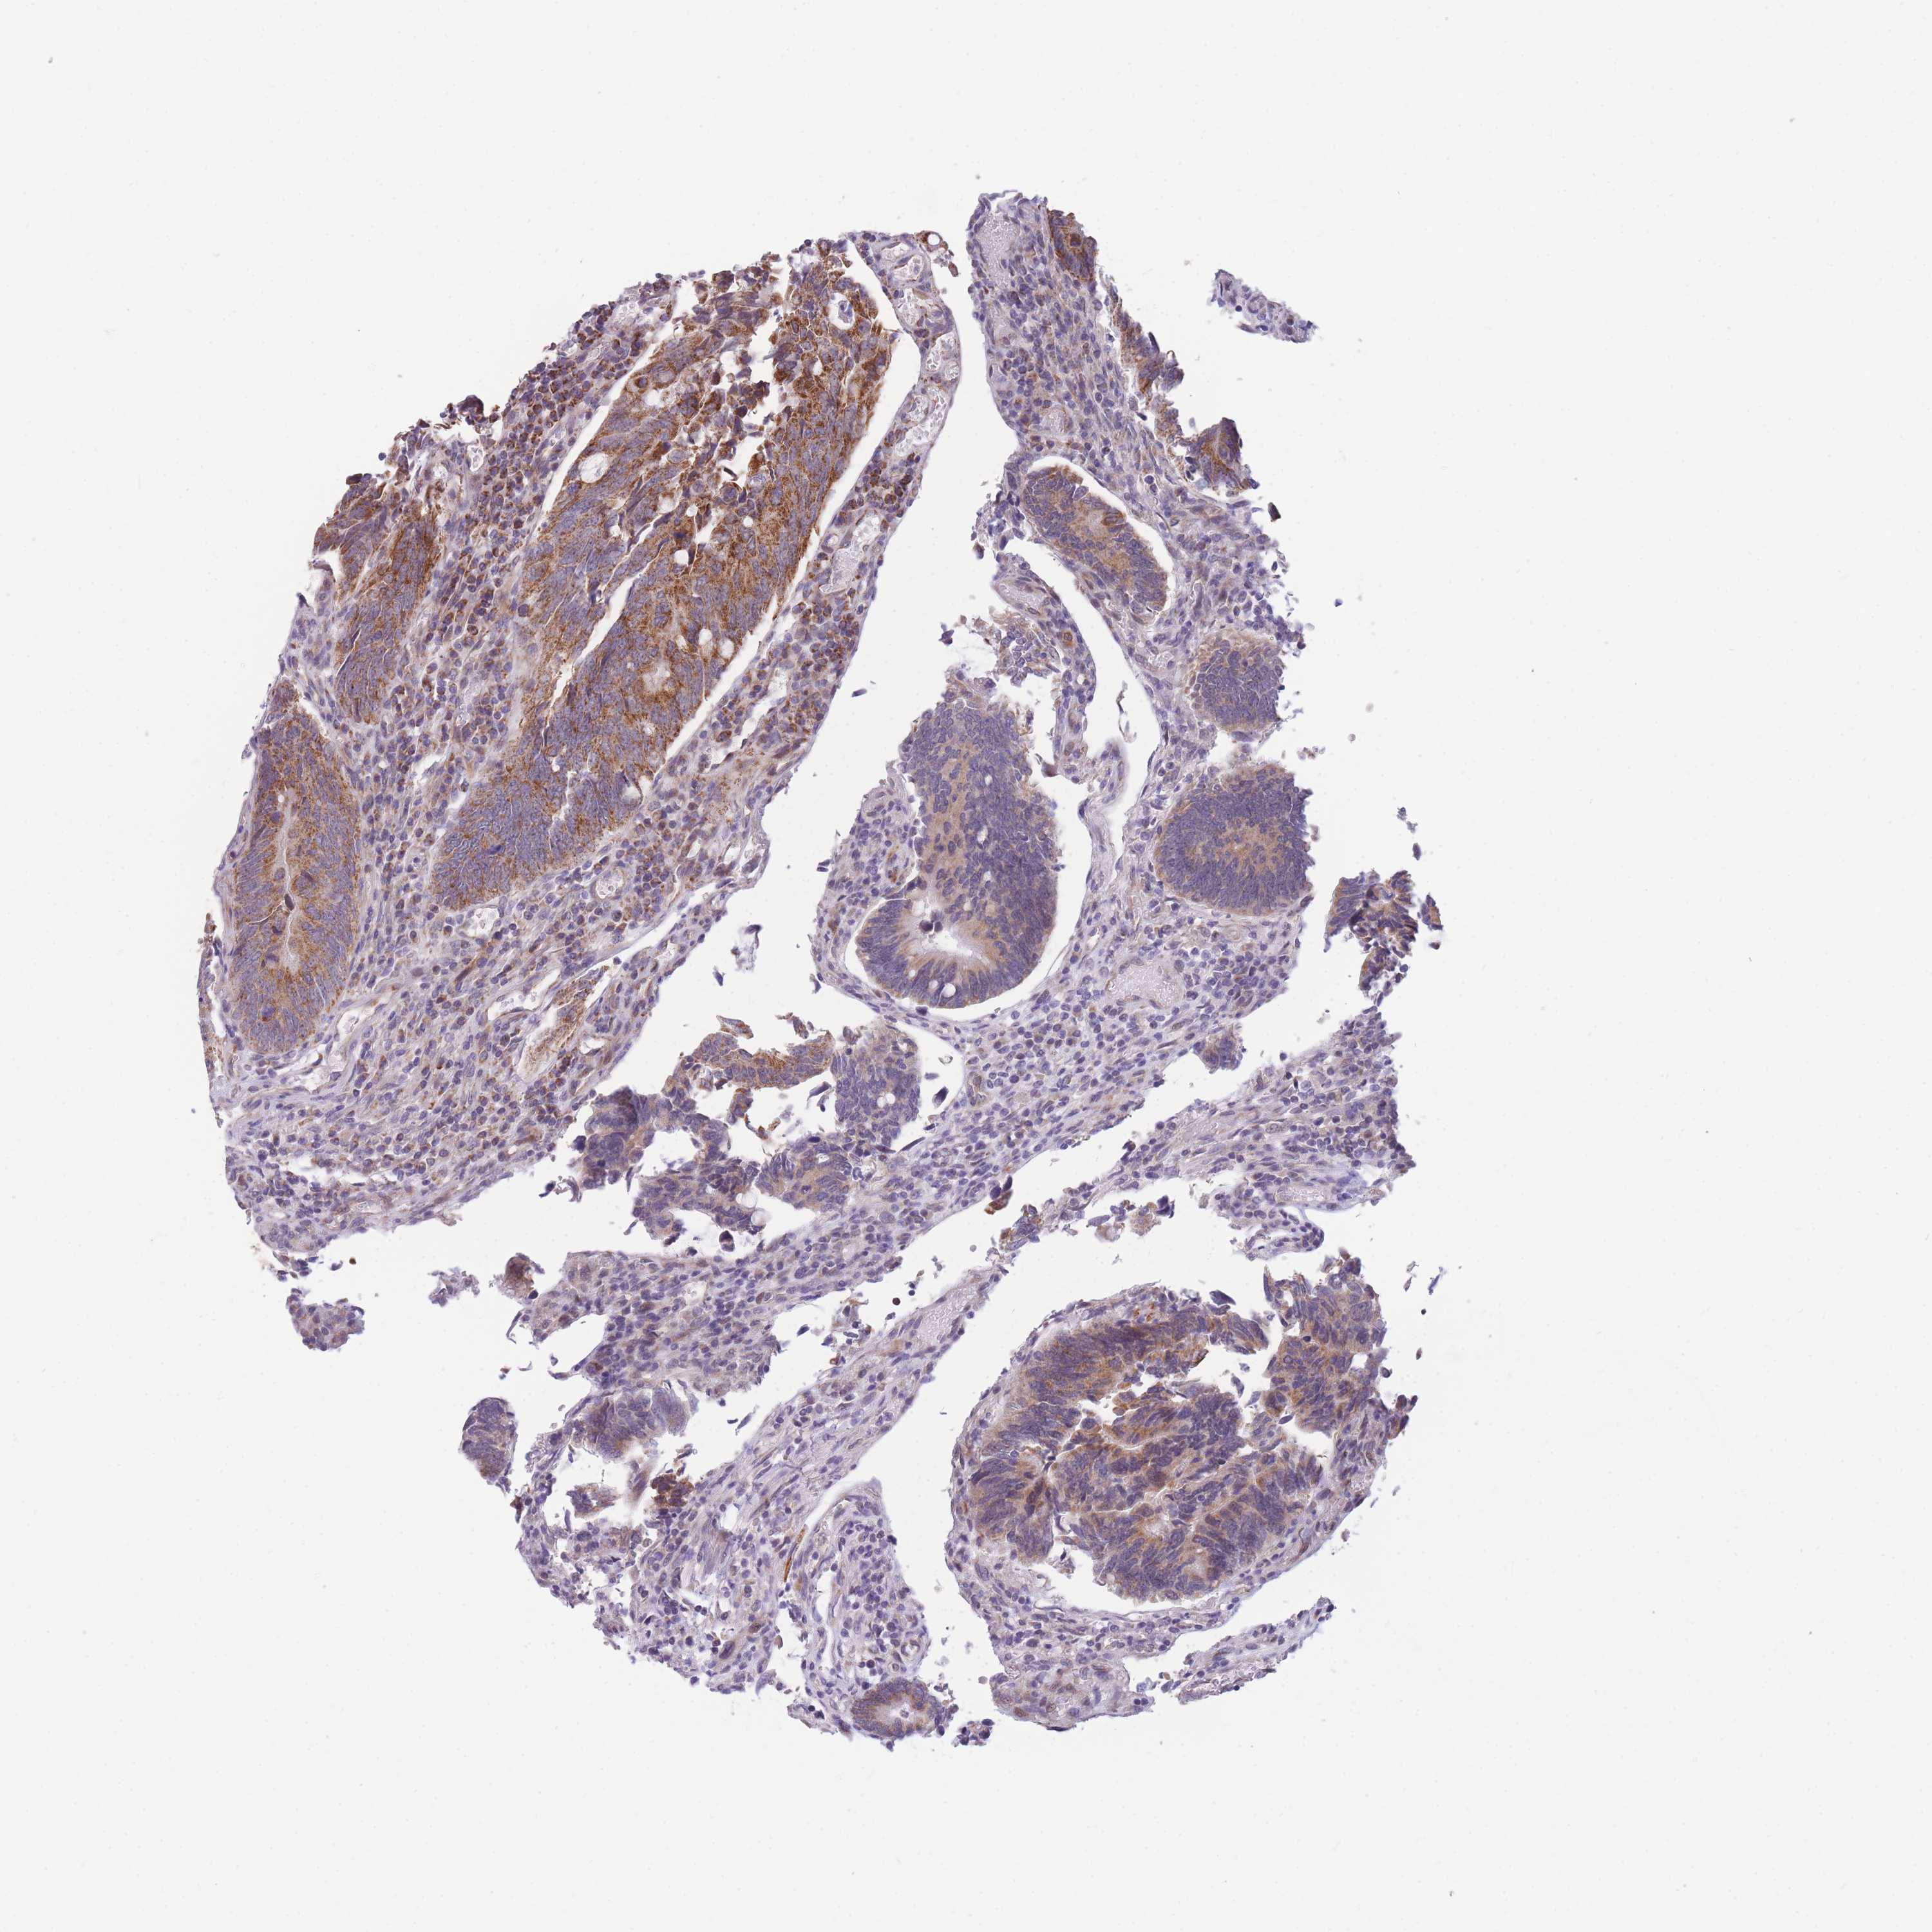

Colorectal cancer

Rectum adenocarcinoma